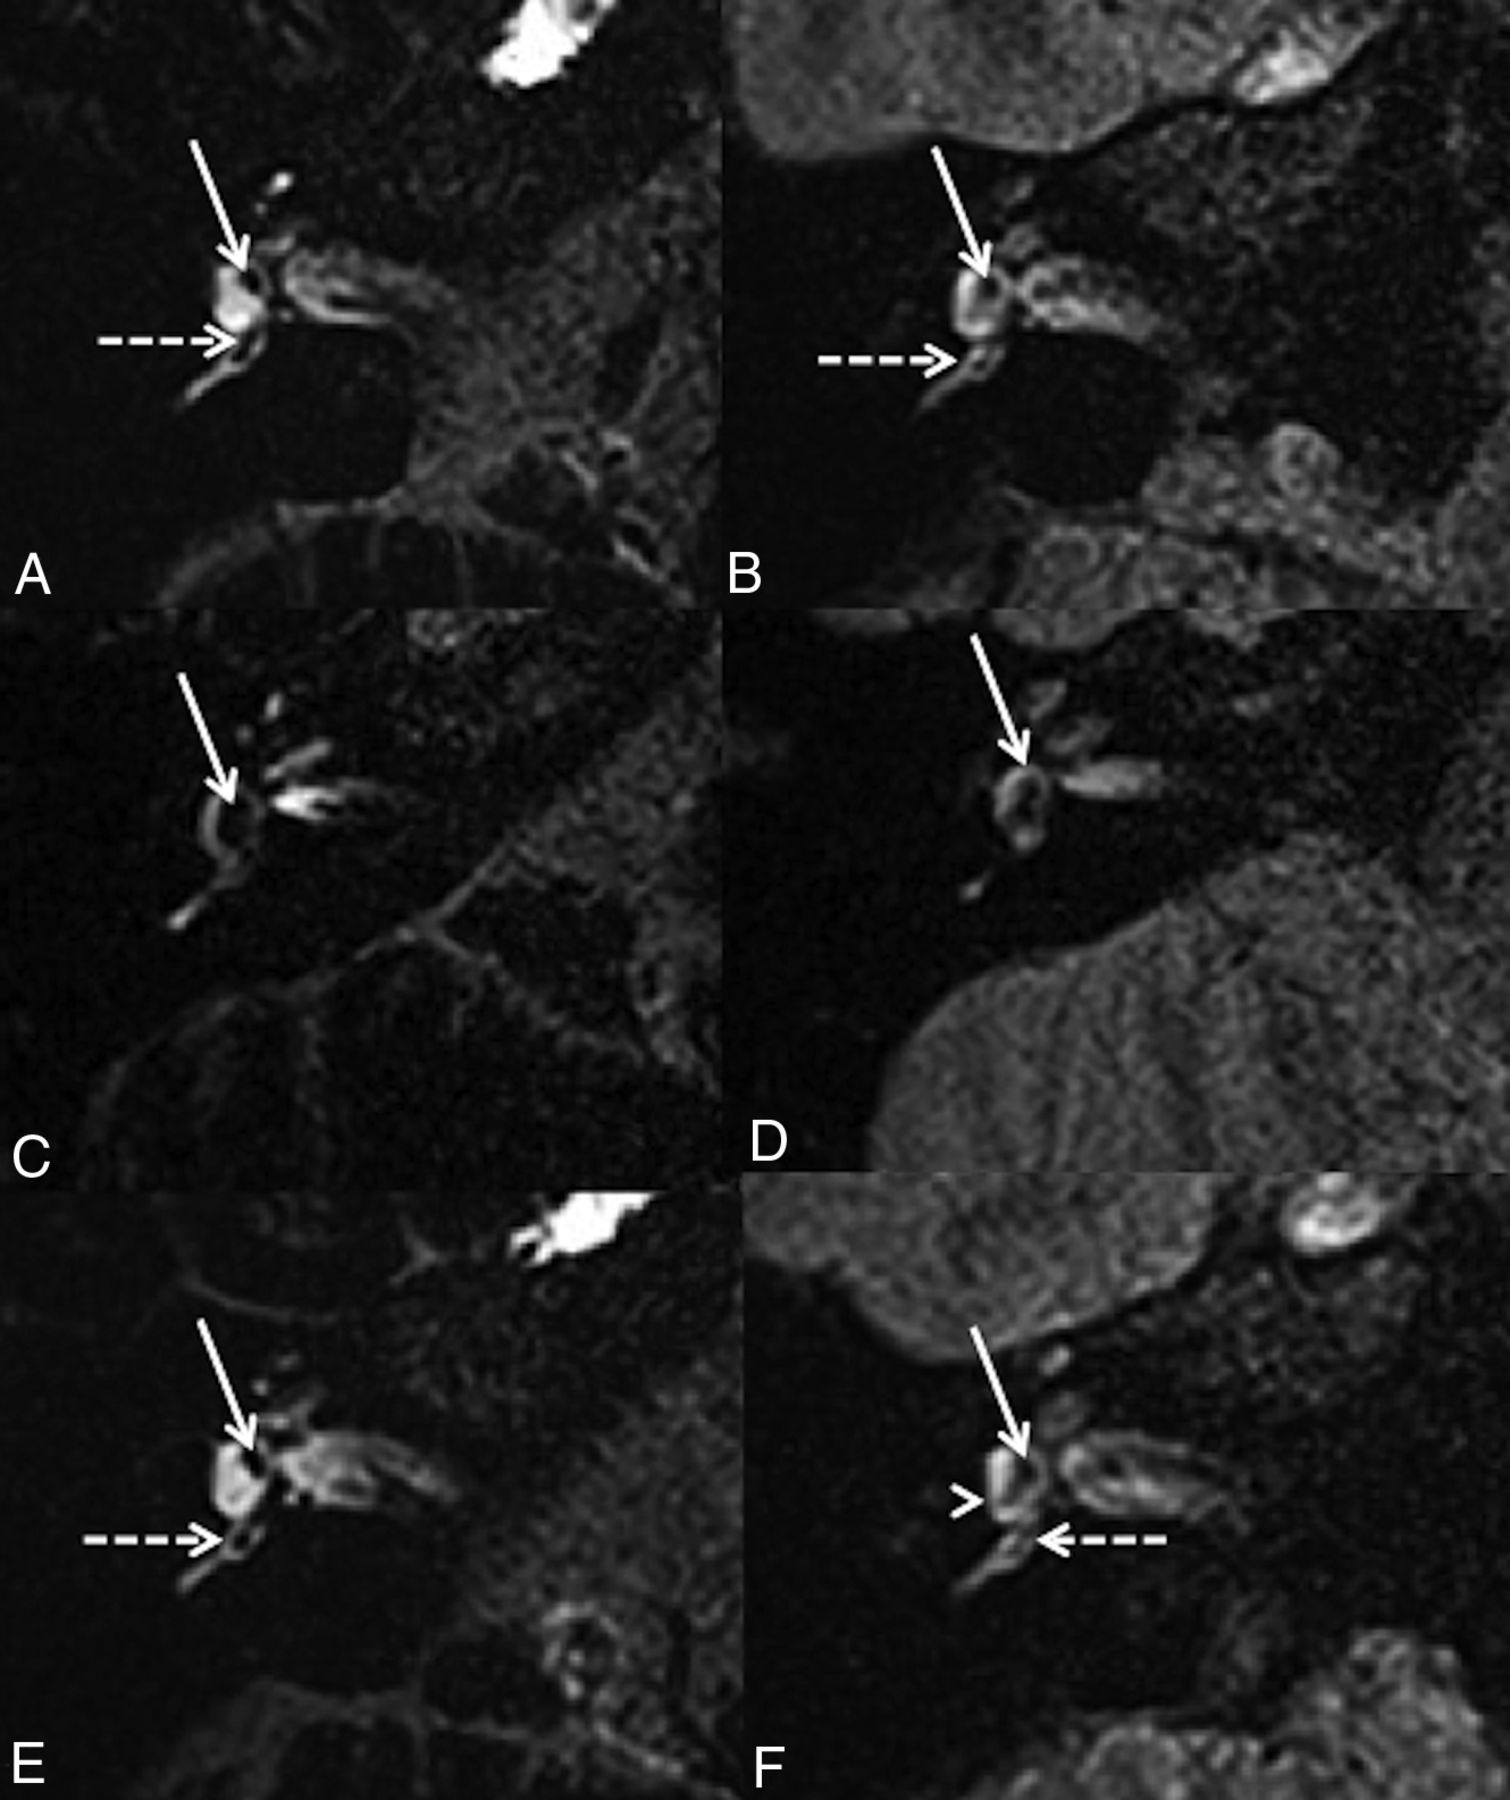

With hVFA sequences (Fig 3), EH was observed in 13/32 ears (40.6%) according to reader A (10/19 symptomatic and 3/13 asymptomatic ears) and 10/32 ears (31.3%) according to reader B (7/19 symptomatic and 3/13 asymptomatic ears). The Cohen κ coefficient was 0.26. There was no significant association between the clinical symptomatology and the presence of EH (P = .15, OR = 3.55; 95% CI, 0.63–26.62; and P = .47, OR = 1.90; 95% CI, 0.32–14.47, according to readers A and B respectively).

A 42-year-old woman with right possible MD. Right axial CFA (A) and hVFA (B) sequences through the inferior part of the vestibule show a normal saccule (white arrow) and posterior ampulla (white dotted arrow) in both sequences. A 43-year-old man with a right definite MD. Right axial CFA (C) and hVFA (D) sequences through the inferior part of the vestibule show saccular hydrops (white arrow) in both sequences. A 35-year-old woman with a right possible MD. Right axial CFA (E) and hVFA (F) sequences through the inferior part of the vestibule and the posterior ampulla (white dotted arrow). With the CFA sequence, the right saccule appears normal (white arrow). With the hVFA sequence, reader A described a right saccular hydrops, while reader B defined the right saccule as normal. The saccule (white arrow) and the posterior and lower parts of the utricle (white arrowhead) were confluent without expansion of these 2 structures.

With CFA sequences (Fig 3), both readers reported EH in 14/32 ears (43.7%: 12/19 symptomatic and 2/13 asymptomatic ears). The Cohen κ coefficient was 1. We found a significant association between the clinical symptomatology and the presence of EH (P = .01, OR = 8.73; 95% CI, 1.33 − 103.73).

Endolymphatic Space Evaluation.

With hVFA sequences (Fig 3), the distinction between the utricle and the saccule was not possible in 13/32 ears (40.6%) according to reader A (8/19 symptomatic and 5/13 asymptomatic ears) and 13/32 ears (40.6%) according to reader B (9/19 symptomatic and 4/13 asymptomatic ears). The Cohen κ coefficient was 0.35. For both readers, there were no significant differences in the distinction between the utricle and the saccule whether the patient was symptomatic or not (P = 1 for reader A and P = .47 for reader B). Among the ears in which the distinction between the saccule and the utricle was not possible, EH was described in only 6/13 ears (46.2%) according to reader A and 9/13 ears (69.2%) according to reader B.

The distinction of the posterior ampulla was not possible in 12/32 ears (37.5%) according to reader A (8/19 symptomatic and 4/13 asymptomatic ears) and 10/32 ears (31.3%) according to reader B (8/19 symptomatic and 2/13 asymptomatic ears). The Cohen κ coefficient was 0.31. The distinction of the lateral ampulla was not possible in 17/32 ears (53.1%) according to reader A (10/19 symptomatic and 7/13 asymptomatic ears) and 21/32 (65.6%) according to reader B (12/19 symptomatic and 9/13 asymptomatic ears). The Cohen κ coefficient was 0.49. For both readers, the absence of discrimination of the ampullas was not significantly related to the clinically symptomatic ear or the presence of endolymphatic hydrops.

With CFA sequences (Fig 3), the distinction between the utricle and the saccule was not possible in 10/32 ears (31.3%) for both readers (9/19 symptomatic and 1/13 asymptomatic ears). The Cohen κ coefficient was 1. Among the 10 ears in which the distinction between the utricle and the saccule was not possible, EH was identified in all ears according to both readers. There was a significant association between the absence of utricle/saccule discrimination and the clinically symptomatic ear (OR = 0.09; 95% CI, 0.01–0.93; P = .02).

The distinction of the lateral and posterior ampullas was always observed for both readers. Interreader agreement was perfect (Cohen κ coefficient = 1).